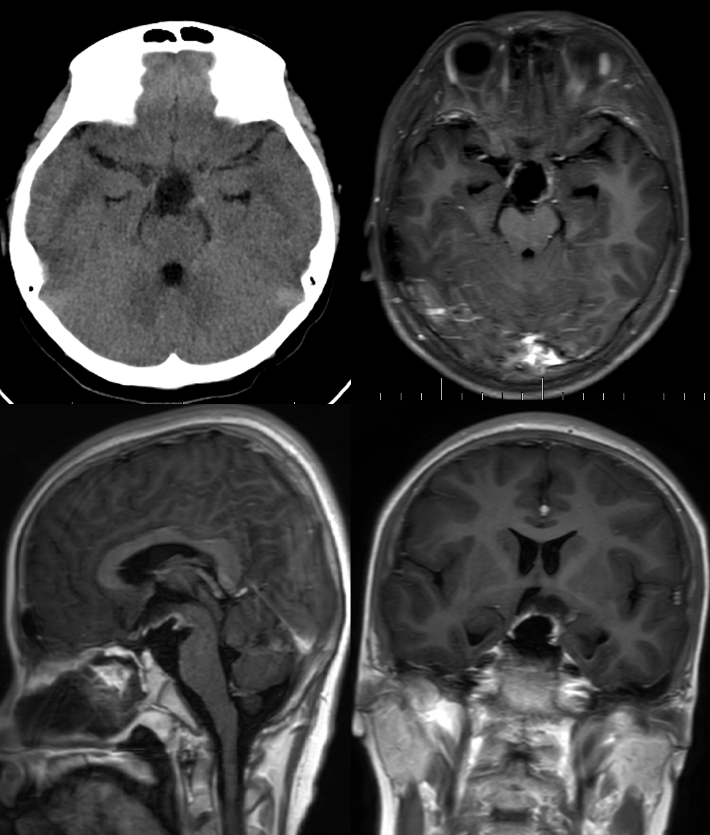

图2.术后当天头部CT及术后一周头部MRI T1增强矢冠轴位